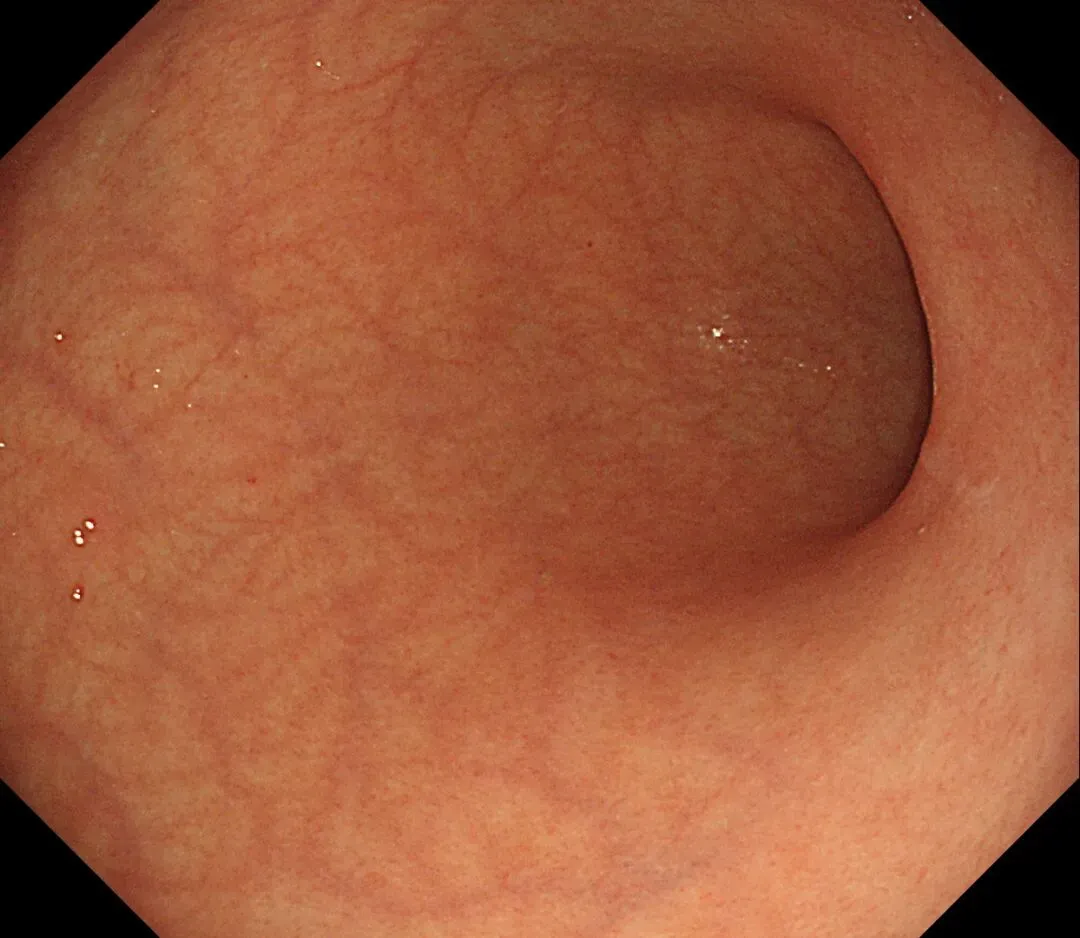

这一期不用码字,挺好的,很可惜一直没机会听过胡导讲的关于这个“花环征”的大课,学习内容来源于雨夜大师的号花环征:AIG背景的胃食管结合部的黄色颗粒状隆起及半透明“泡状”改变

补充自己在两例A型胃炎/AIG 观察到的“花环征”,巩固下学习效果。。。

case1:

1.白光表现为胃食管交界处黄色颗粒状隆起及半透明“泡状”改变

2.窄带光下可见颗粒状隆起呈褐色改变,放大可见细微网状血管结构及半透明“泡状”改变

3.典型病理是鳞状上皮局灶性变薄及黏膜固有层显著增生、扩张的贲门腺。